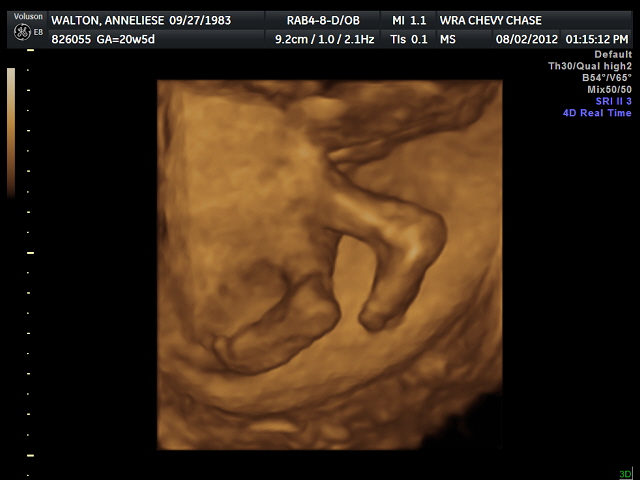

IT'S (SHE'S) A GIRL!!!

Last week we finally found out the gender of our child. It's a girl! wooooot! We are excited, Liese is already working on a girly baby blanket.

This is the evidence, I'm convinced.

She kept licking the wall of the placenta, we're going to have one of those weird kids that licks everything....